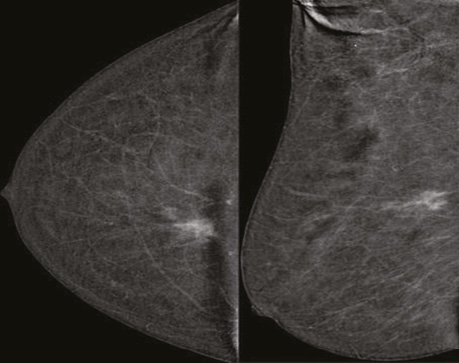

При аналізі низькоенергетичного зображення в динаміці в правій МЗ на 1 год ретромамарно зменшився розмір таргетного вузлового новоутворення до 22×13×18 мм, знизилися його щільність, інтенсивність та інфільтрація паренхіми перинодулярно. Інших вузлових новоутворень на низькоенергетичних сканах не виявлено (рис. 4).

Рис. 4. Площинна мамографія в R-MLО- та R-СС-проєкціях після 4 курсів НХТ. Зменшилися розмір, щільність та інтенсивність гетерогенного вузлового новоутворення ретромамарно

У правій аксилярній ділянці лімфатичний вузол розміром 21×9 мм, кірково-медулярна диференціація простежується, кірковий шар нерівномірний, потовщений до 3,2 мм.